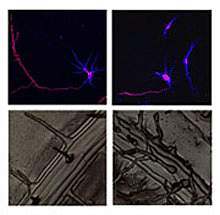

Sprouting. Branching. Pruning. Neuroscientists have borrowed heavily from botanists to describe the way neurons grow. A new study suggests the analogies may be more than superficial. Neurons and plant root cells may grow using a similar mechanism. The research sheds light on a group of inherited neurological disorders called hereditary spastic paraplegias (HSP).

Arabidopsis has a gene comparable to atlastin called Root Hair Defective 3 (RHD3). Mutations affecting RHD3 cause the plant to grow short, wavy root hairs.

Arabidopsis could prove to be a useful tool for investigating HSP. It's easy to raise in the lab, and the short root hairs of the RHD3 mutant can be readily observed. Blackstone says he hopes to collaborate with other scientists to develop strategies to correct root hair defects in the RHD3 mutant. These might provide valuable therapeutic insights into HSP.